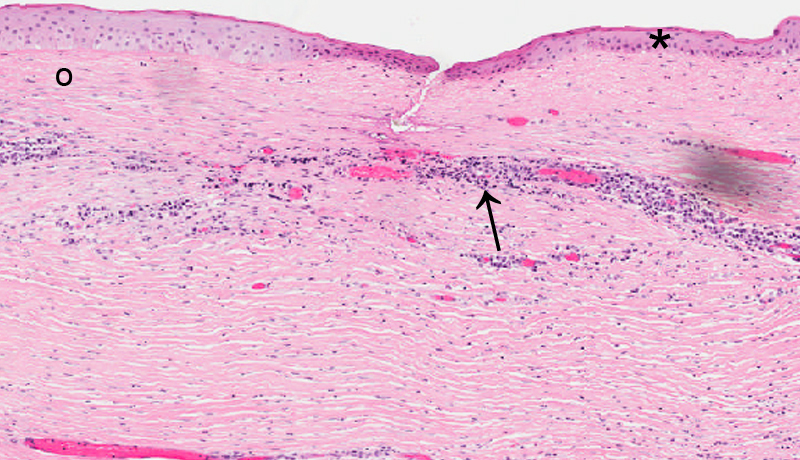

DISEASE: Corneal interstitial keratitis

PATHOGENESIS: Nonsuppurative inflammatory cell infiltration interlamellar spaces of corneal stroma. Transplacental infection of Treponema pallidum can cause. Other organisms: mycobacterium tuberculosis, mycobacterium leprae, borrelia burgdorferi, EBV, Herpes most common.

HISTOLOGY FEATURES: Bowman's usually absent. Stroma free of inflammation and find blood vessels do not contain blood. Descemet's membrane may be massive. Relucent strands and networks of basement membrane material are found on posterior corneal surface.